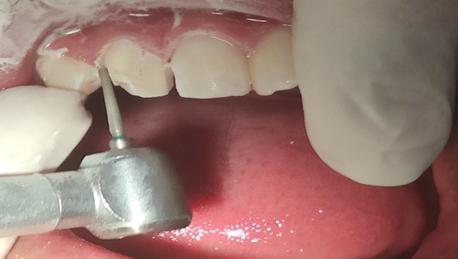

FASE DE ENDODONCIA

Se administró anestésico local de Lidocaína al 2% con epinefrina 1 en 80mil partes de millón, con la técnica infiltrativa supra perióstica con cierre de circuito por palatino. Para el acceso se tuvo en cuenta la forma, dirección y el tamaño de la cámara pulpar observada en la radiografía inicial; se accedió al conducto por palatino con fresa redonda de diamante mediana (0,18) (Fig. 3A y 3B). Se

realizó la extirpación del tejido vasculonervioso con tira nervios de distintos calibres, posteriormente fue realizada la conductometría una vez verificada esta, se realiza la preparación biomecánica con limas tipo

K de 25 mm desde la lima 15 hasta la 40, realizando irrigación copiosa con hipoclorito de sodio al 2.5 % (Fig. 3C, 3D, 3E y 3F).

Figura Nº3. A y B Acceso al conducto radicular por la cara palatina de la pieza con fresa de carburo. C y D Extirpación del paquete vasculonervioso. E y F Conductometría.

Fuente: Elaboración propia, septiembre 2021.

FASE PROTÉSICA

El desgaste en la superficie vestibular comenzó realizando guías de 1 mm de profundidad con fresa fisura, a nivel del borde incisal se realizó las guías con una profundidad de 2 mm, la reducción de las superficies proximales fue de 1 mm de grosor preservando el paralelismo, hacia palatino

se redujo 1mm siguiendo la morfología de la pieza dentaria especialmente a nivel de la concavidad palatina, la delimitación cervical de la preparación por vestibular y palatino siguió la curva parabólica de la encía realizándose un desgaste de 1 a 2 mm supragingival (Fig. 5A, 5B y 5C).

Figura Nº5. A, B y C Preparación de la pieza 1.2 para posterior rehabilitación con prótesis fija unitaria. A B C